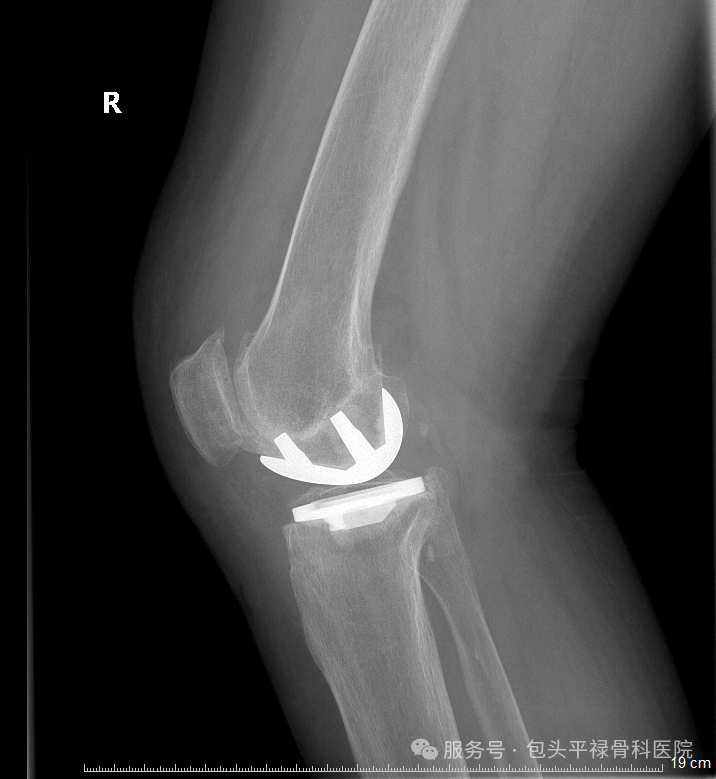

以单髁置换术为例:只换掉膝盖里磨损严重的房间“地板”,保留健康的墙壁、承重梁和隔壁房间。

1.这不仅仅是“少换一点”那么简单,它意味着:

2.创伤更小:切口更短,切除的骨头更少,出血少

3.恢复更快:术后当天或第二天就能下地,大多数患者术后一到三个月即可逐步回归日常生活

4.感觉更自然:保留原膝所有重要的韧带,运动时的本体感觉几乎和原来一样

5.未来选择更多:即使若干年后保膝手术的效果减退,仍然可以考虑进行全膝关节置换,比全膝置换的翻修要简单得多